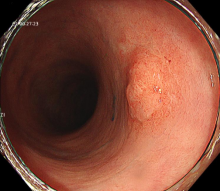

图示:结肠高分化腺癌:镜下呈隆起病变,放大内镜观察:表面结构不规则,微血管扭曲、紊乱、不规则。